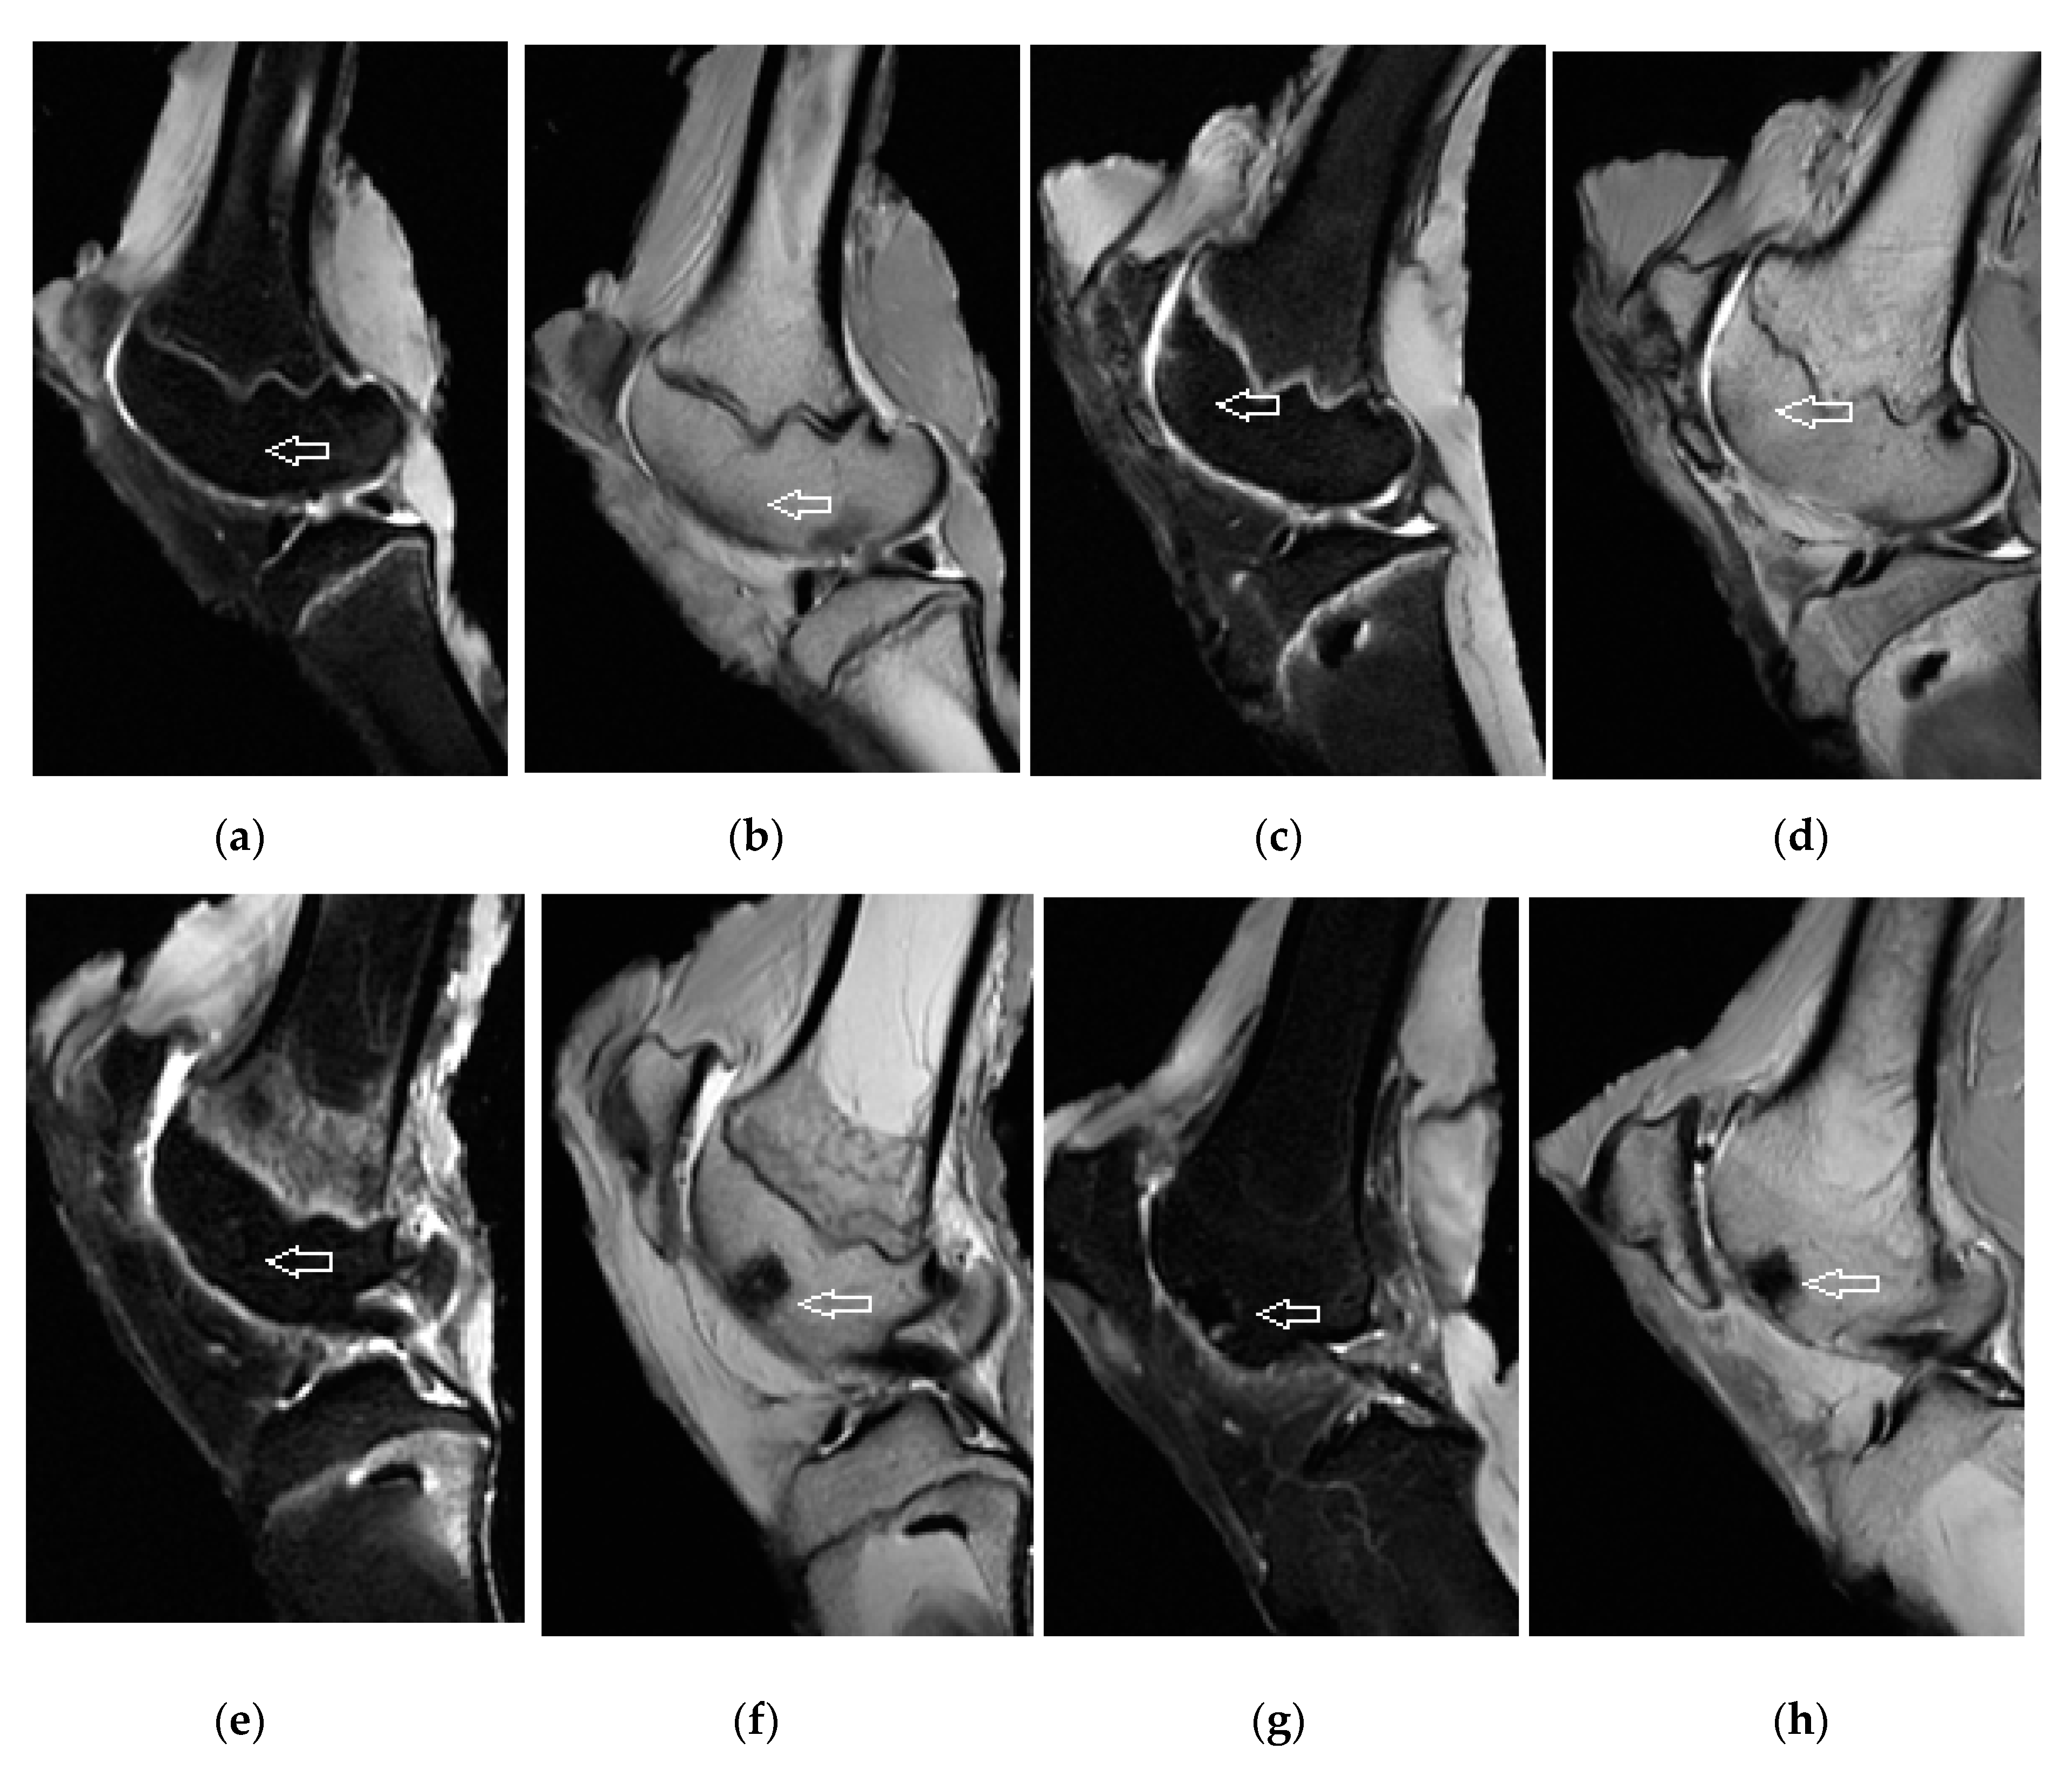

3.3. Magnetic Resonance Imaging Assessment of Cartilage Repair Tissue, Micro-CT and X-ray Evaluation